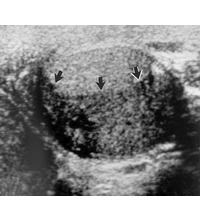

Hodentumore (helle Region – über den Pfeilen) können die Spermienproduktion einschränken.